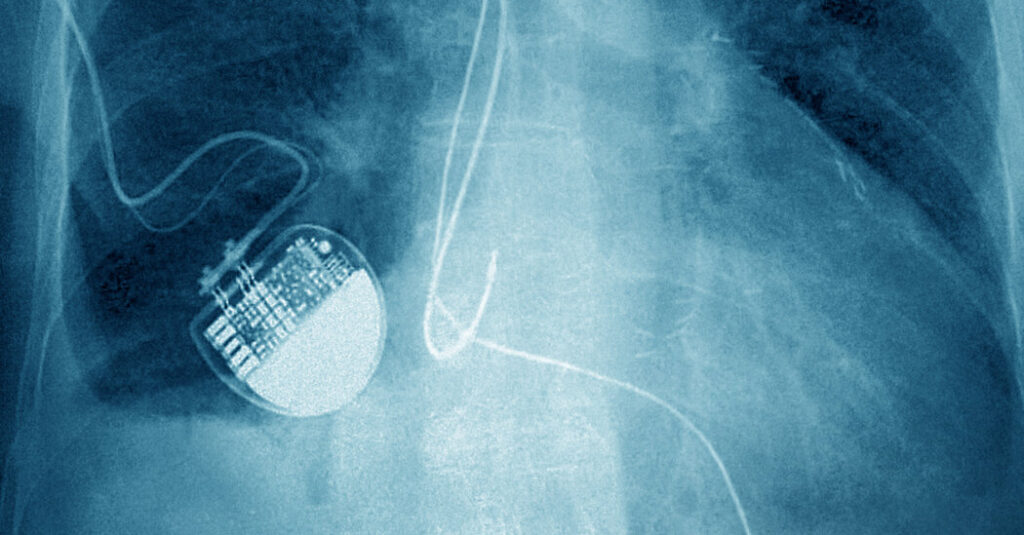

Like an estimated three million Americans, Nancy Guthrie, the 84-year-old mother of the NBC News anchor Savannah Guthrie, has a pacemaker implanted in her chest.

A pacemaker constantly records a person’s heart rate, and uses that data to prevent it from dropping too low. If a person’s lowest heart rate is set to 50, for example, the pacemaker will send painless electronic pulses when the rate drops lower in order to drive it back up (unlike an implanted defibrillator, which shocks a stopped heart).

Pacemakers are constantly recording data, but they do not provide information on a patient’s location, said Dr. Roderick Tung, director of the cardiac electrophysiology program at the Banner — University Medical Center Phoenix in Arizona.

A vast majority of patients use remote monitoring, which involves a device that’s typically placed on a bedside table. In some cases, it is an app on a smartphone. The monitor checks on data stored in the pacemaker throughout the day. Investigators did not say which company made Ms. Guthrie’s device, nor if it uses that method of monitoring.

In order for pacemaker data to be sent to the monitor, the person needs to be close by — typically no more than about 10 feet away, Dr. Tung said.